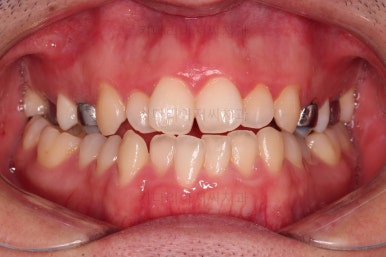

부산긴얼굴긴턱교정 전후 비교해 볼게요.

이렇게 비교해 놓으니 더 드라마틱하죠.

당연히 교합/위아래 폭 등 치열이 좋아졌고요.

얼굴 모습에서도 주걱턱이 개선되었고, 긴얼굴, 긴턱 등 길이 부분도 굉장히 좋아졌습니다.

적절한 협진을 통해서 과하지 않게 특유의 양악수술 느낌의 어색함 없이 개선이 잘 되었습니다.

얼굴 길이가 짧아지면 이렇게 훨씬 어려보이는 효과도 주게 됩니다.